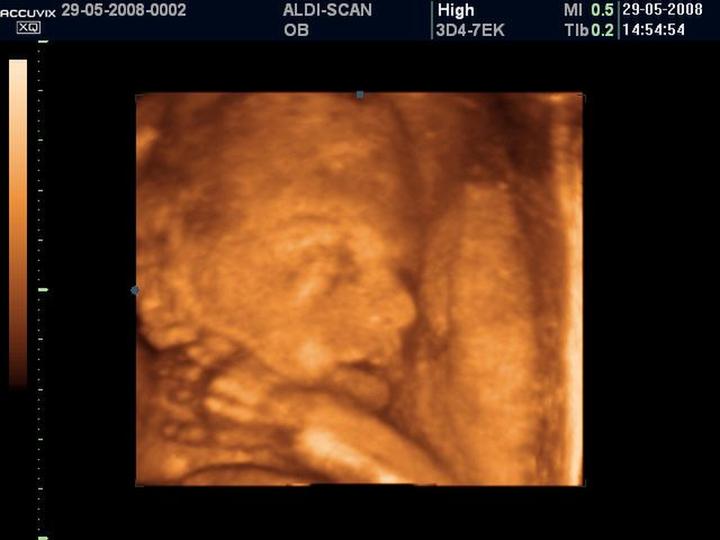

W 27. tygodniu ciąży twoje maleństwo nabiera tempa, niczym mały pociąg ekspresowy, który ruszył na ostatnią prostą w stronę stacji „Świat”. Możesz zauważyć, że bobas nie tylko rozróżnia światło i ciemność, ale również ostrożnie otwiera i zamyka powieki. Zaczyna to wyglądać jak jego mała sztuczka, w której pyta: „Czy widzisz mamę? A teraz mnie nie widzisz!”. Poza zabawami w chowanego, maluch podejmuje także misję kulinarną, ponieważ dzięki rozwojowi kubków smakowych jest w stanie odczuwać smaki płynu owodniowego, co sprawia, że na jego „menu” mogą pojawić się subtelne nuty z twojej diety!

W tym tygodniu skóra twojego malucha wciąż pokazuje oznaki pomarszczenia, co wynika z braku tkanki tłuszczowej. Nie martw się jednak, bo już wkrótce zacznie przybierać na wadze jak mały trener kulturysty! Jego organizm gromadzi tkankę tłuszczową, aby wyglądać bardziej jak „mały grubasek”, co jest popularnym żartem ze strony złośliwych osób. Waga bobasa wynosi około 1 kg, a jego długość to zaledwie 34 cm – tak, obecnie przypomina wielkością kalafiora!

W ostatnich tygodniach ciąży, zwłaszcza w 27. tygodniu, Twoje dziecko rozwija się w tempie zawrotnym! W tym momencie maluch zaczyna otwierać powieki, co oznacza, że dostrzega światło, cienie, a być może nawet Twoje wieczorne tańce w kuchni. Z pewnością każdy napotkany blask kuchennego żyrandola sprawi, że zacznie mrugać jak prawdziwy VIP! Dodatkowo, mały skarb trenuje umiejętności związane z odczuwaniem smaków. Smaki, które mu dostarczasz, przenikają do płynu owodniowego, więc jeśli ostatnio serwowałaś mu oryginalne i pikantne potrawy, to nie zdziw się, gdy odbierzesz od niego kilka dynamicznych kopniaków. To wyraźny sygnał, że Twoje dziecko ma swoje zdanie!